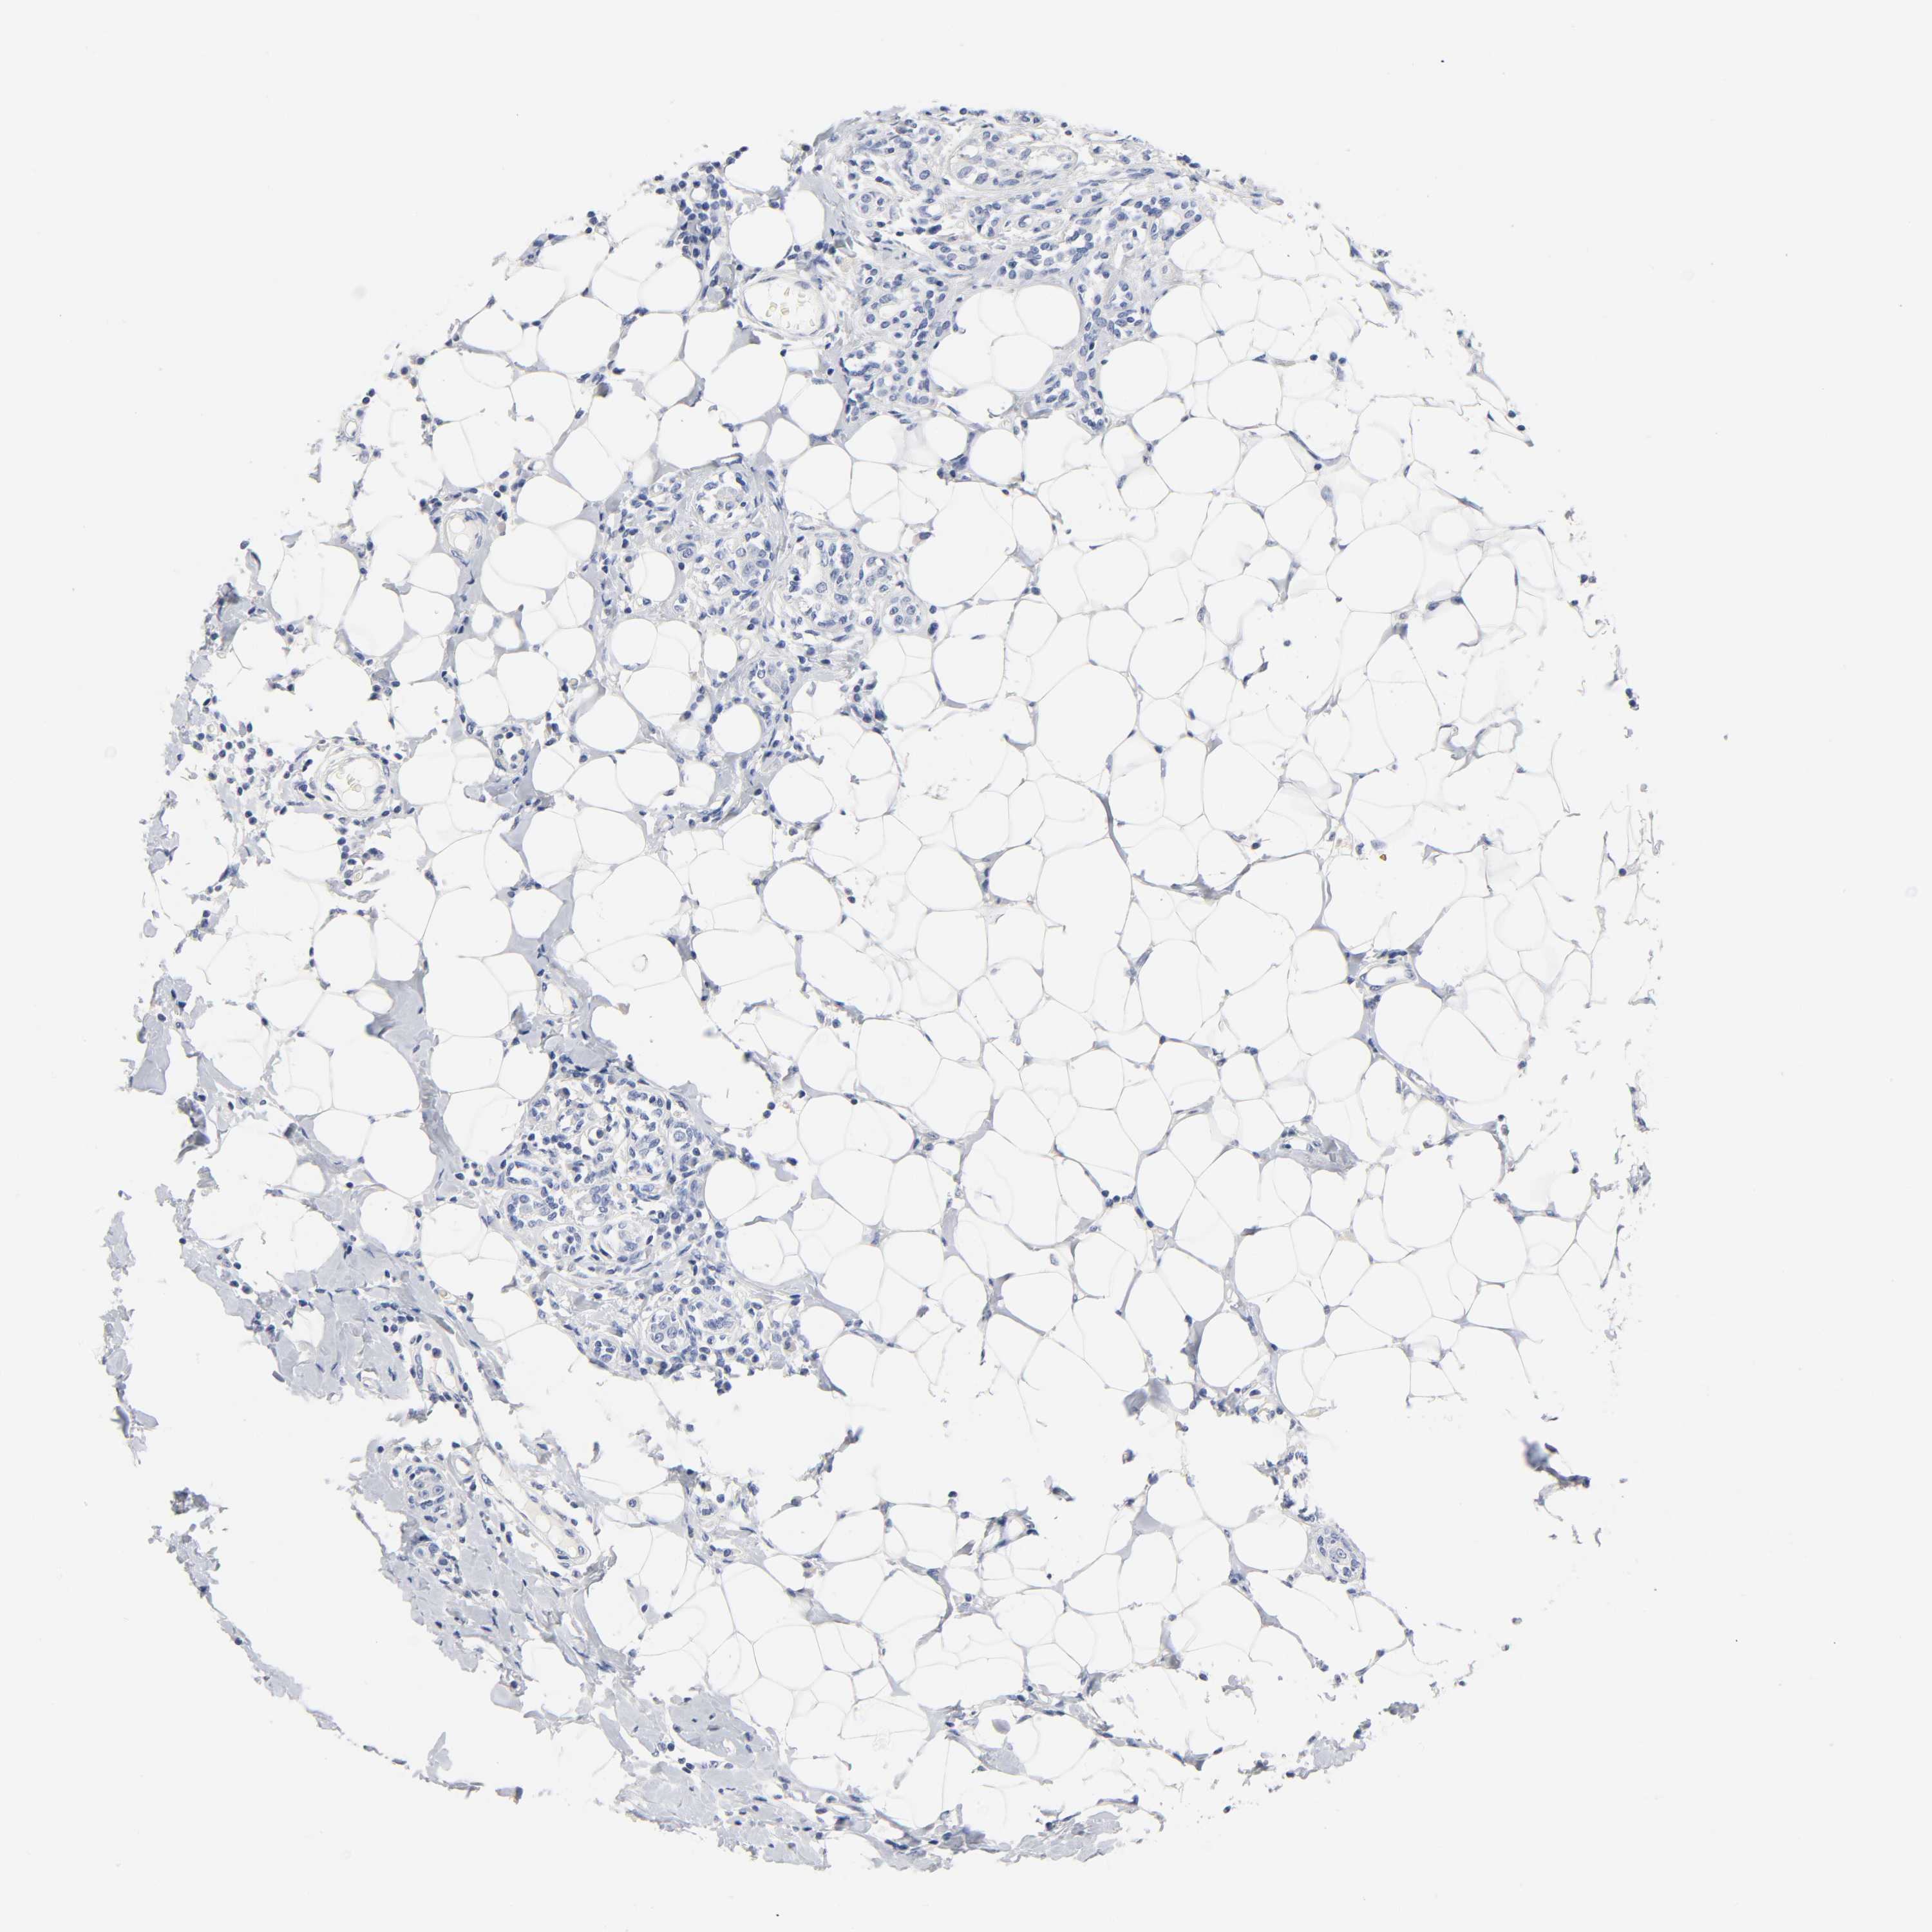

BRCA TCGA BRCA VALIDATION PROTEIN EXPRESSION

ANTIBODIES

AND

VALIDATION